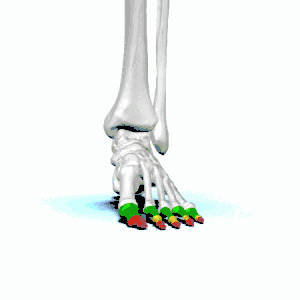

Fractures of the smaller toes are commonly treated by buddy taping (see image). Padding is used between the toes to keep the space dry[4] and the toes aligned comfortably. If the toes are less comfortable when buddy-taped, the buddy tape should be removed.[7] Taping is not recommended for those with diabetes or peripheral arterial disease.[7]